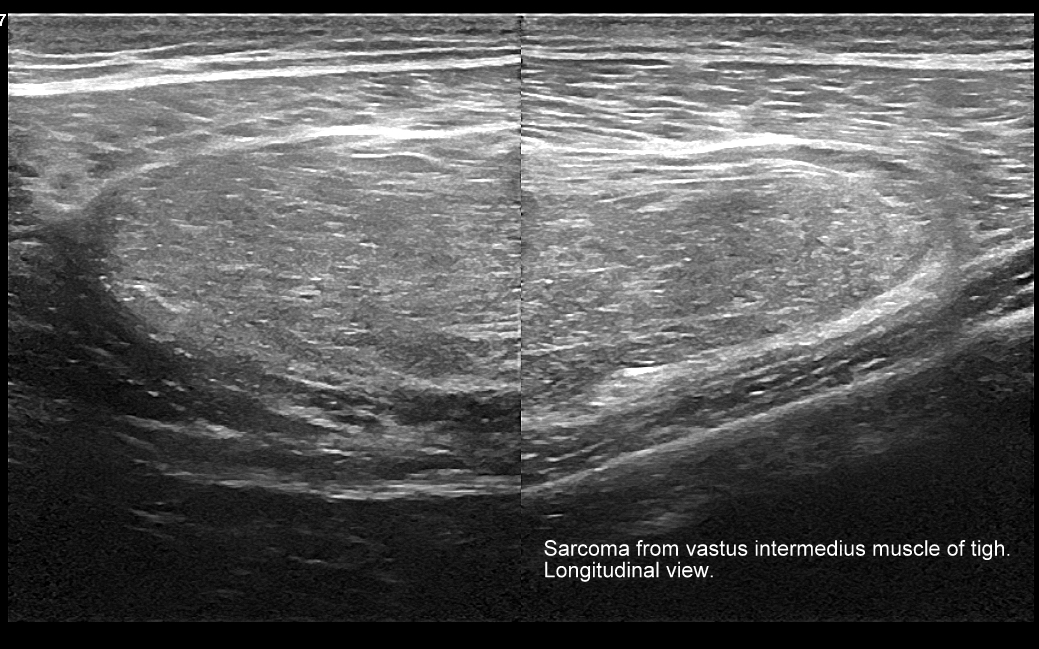

Badanie USG w obrębie uda najczęściej wykorzystywane jest przy diagnostyce urazów sportowych, wśród których dominują naderwania mięśni. Naderwania u dorosłych lokalizują się zwykle w okolicy przyczepu bliższego mięśnia czworogłowego uda, przyczepów bliższych i dalszych tylnej grupy mięśniowej (mięśnie półbłoniasty, półścięgnisty, dwugłowy uda) określanej zbiorczo z języka angielskiego jako hamstringi, a także w obrębie mięśni przywodzicieli. W mięśniach uda nierzadko u młodych dorosłych pojawiają się nowotwory mięsaki. U dorastających dzieci naderwania w zakresie jednostek ruchowych występują na przyczepach ścięgnisto-chrzęstnych lub chrzęstno-kostnych.